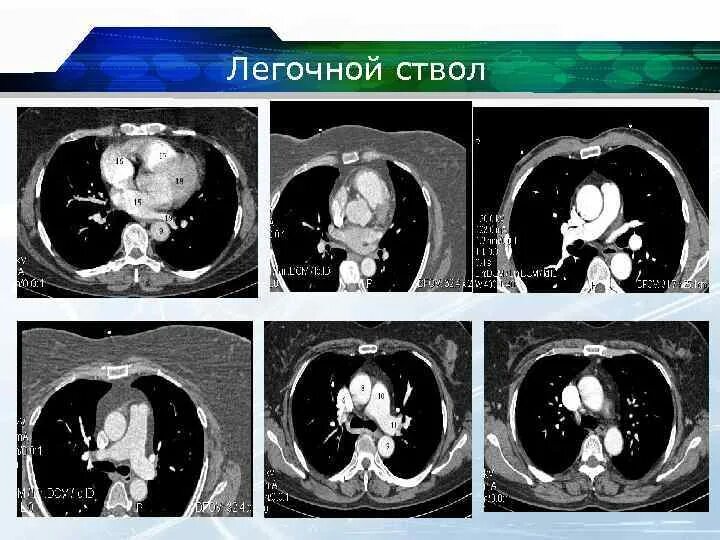

Легочный ствол на кт